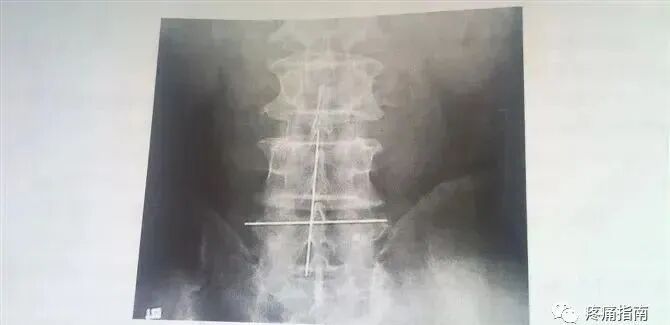

2、依据骨性标志,在病变间隙及脊柱后正中线放置金属标志针。标志针要求以紫药水涂均,用胶布固定至皮上,拍腰椎正位X线平片。

3、在腰椎正位X线平片上等比例测量带有标志线的后正中线至椎板外切迹或小关节内、外缘、小关节间隙的横向距离;由于棘突不一定完全在后正中线上,所以在后正中线上放金属标志线,测量横标志线距进针点的纵向距离。

4、测量X线平片上金属线至进针刀的距离。

5、测量染色金属线在体表留下的标记至进针刀点的距离进行体表定位。

(二)经300例病人测量的数据平均值为:

1、后正中线至小关节内缘一般在1.2-1.5cm,小关节间隙一般在1.5-2.0cm,椎板外切迹一般在1.7-2.2cm。

2、进针达侧隐窝深度,小关节内缘一般不超过5.8cm,小关节间隙一般不超过6.8cm,椎板外切迹一般不超过6.2cm。可作为临床参考。